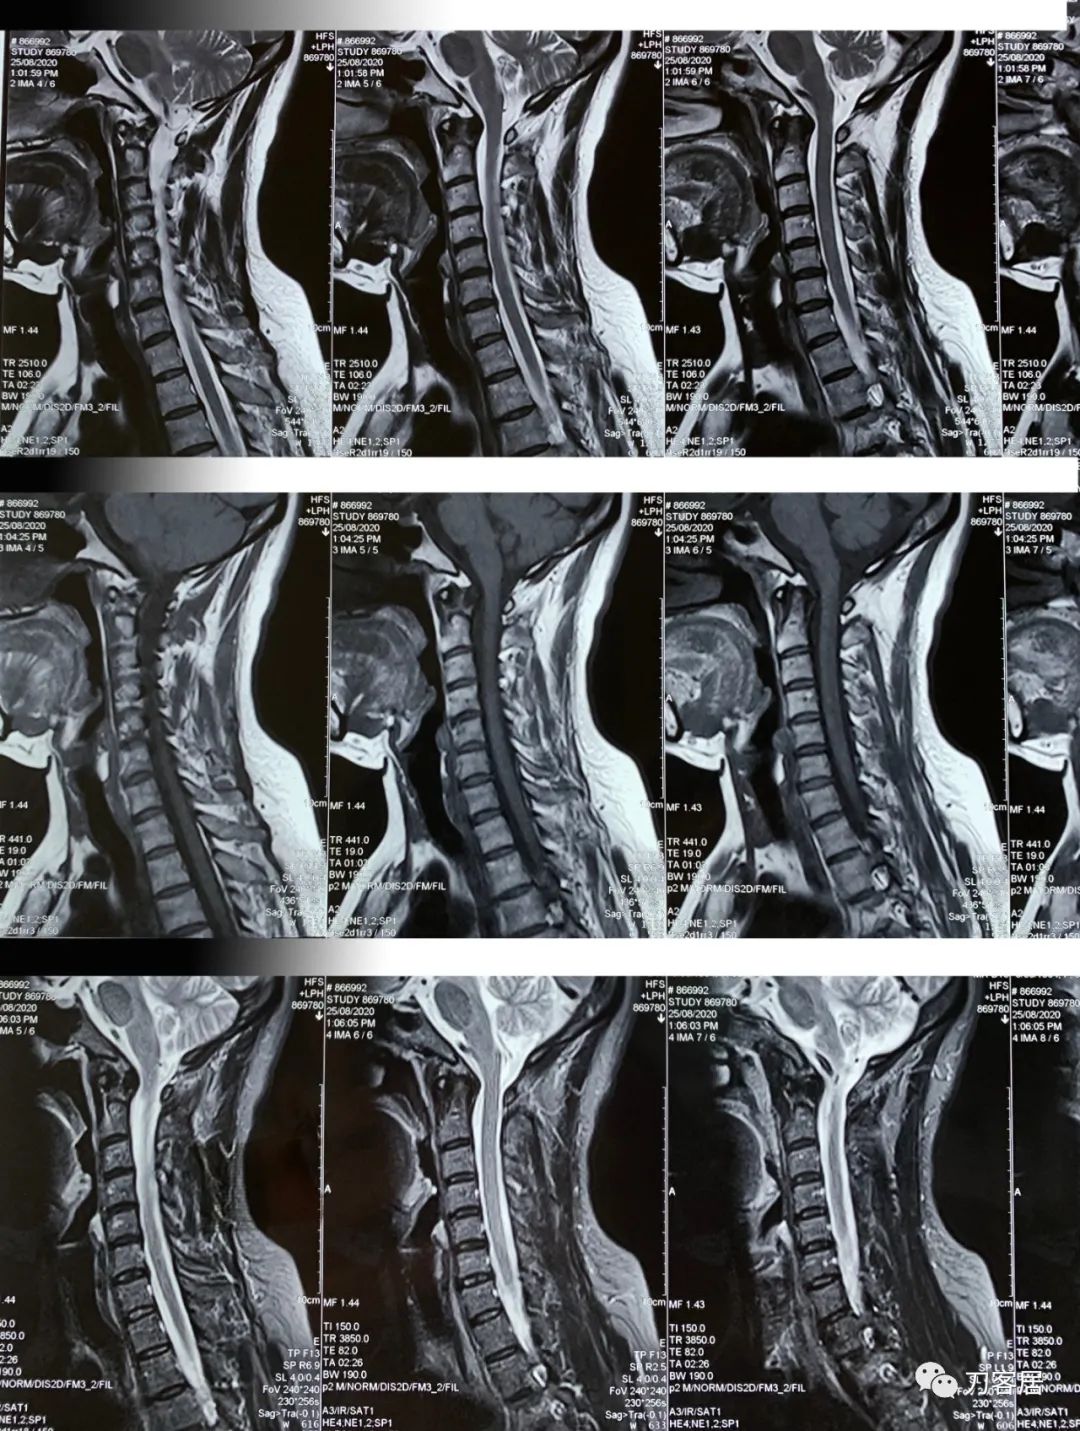

患者自2020年8月4日始头晕,2020年8月25日双手麻,双胳膊麻,于兰大二院定西分院检查颈椎MRI及腰椎X线片, 提示1. 颈椎生理曲度变直,2. 颈椎骨质增生,3. 颈椎间盘变性,颈4-7椎间盘轻度膨隆,4. 腰椎侧弯畸形。

从这个患者的影像资料分析,颈椎间盘突出问题不大,没有明确的上位神经元损伤表现,所以,不考虑颈椎和胸椎问题。腰椎侧弯畸形,但不严重。因为存在腰椎侧弯,使得腰椎MRI在扫描切面的时候,显示的椎间盘突出或椎管狭窄会有一定的误差,所以,又加做了经椎间盘的CT平扫,影像表现并不严重,综上,腰椎间盘突出,腰椎管狭窄,腰椎侧弯,不考虑手术治疗。同时,患者的主要痛苦是心理疾病,而不是器质性疾病,所以,以心身疾病治疗为主。虽然患者骨密度检查结果提示正常,但X线片显示骨质疏松,且其症状也与骨质疏松的症状有符合之处,比如静息痛,不能入睡,动作及姿势变换时痛加重等,所以,给予实验性抗骨质疏松治疗,以观疗效。

1. 2020年8月4日因头晕,就诊于兰大二院定西分院,颈椎MRI检查提示颈椎生理曲度变直,颈椎骨质增生,颈椎间盘变性,颈4-5,颈5-6,颈6-7椎间盘轻度膨隆,相应层面硬膜囊受压

2. 2020年8月25日在兰大二院定西分院因手麻,胳膊麻,做了颈椎核磁检查